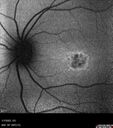

24 year old female She has worn glasses since she was a kid. Since she became an adult her vision started to deteriorate more rapidly. This seems to have been happening since she entered the accounting department for the last two years. Her vision is worse in the light especially when she is driving. She can see green lights in the night but not in the day. She sees better on a dark background than on a light background.

Her mother and father both have inherited retinal diseases. His mother was diagnosed 23 years ago with Stargardts genetically confirmed in Boston. The father has Retinitis Pigmentosa. The mother has seven brothers and sisters and four have Stargardts and they are legally blind. Also one cousin has it.

PMHx benign, Meds: vitamins.

VA OD: Dcc20/160

VA OS: Dcc20/160

IOP: TP: OD:20 OS:21